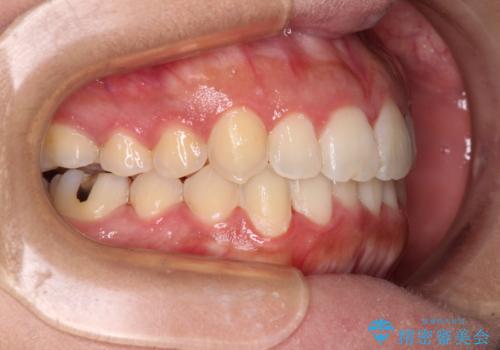

前歯のデコボコをインビザラインでスッキリと

- 上下前歯のデコボコを気にして来院された患者様です。

デコボコを解消する過程で、歯列の拡大により口元が突出する可能性があったため、4本の親知らずを抜歯しておき、歯列全体が後方に移動するように設計し、インビザラインにて矯正治療を行うこととしました。

日々の装着時間をしっかりと守って治療の臨んでくださったため、治療前のシミュレーションに近い形で矯正治療を進めて行くことができました。